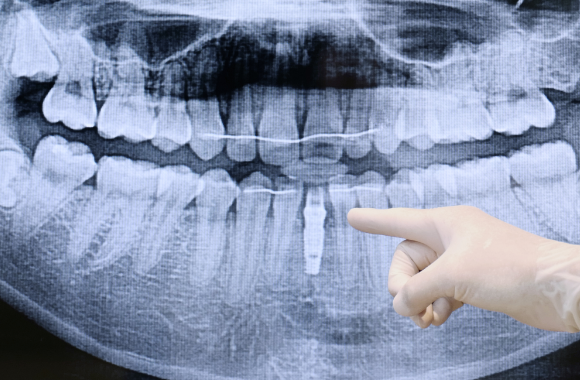

정밀진단

3D 모의 수술을 위해 첨단 장비를 이용하여 환자의 구강 상태, 뼈, 신경의 위치 등의 검사를 진행합니다.임플란트